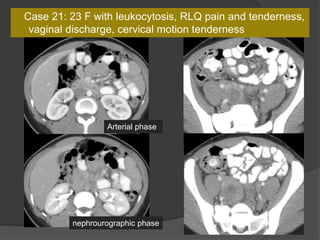

Case 21: 23 F with leukocytosis, RLQ pain and tenderness,

vaginal discharge, cervical motion tenderness

Arterial phase

nephrourographic phase

Dx: TOA with perihepatitis (Fitz-Hugh Curtis Syndrome)

 Characterized by right sided abdominal

pain and perihepatitis associated with

pelvic inflammatory disease (gonococcal

or chlamydial)

 Localized RUQ peritonitis (hepatic

capsular/pericapsular enhancement on

the arterial phase) with PID (mild pelvic

edema, thickened fallopian tubes,

enlarged ovary, abnormal endometrial

enhancement and fluid, frank

tuboovarian abscess) suggest the

diagnosis